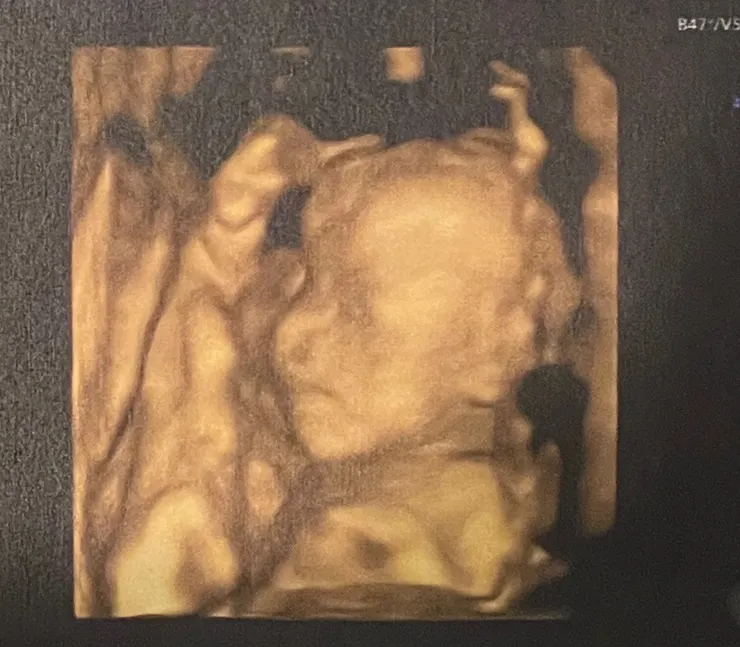

這是(第二胎),小小寶始終是趴躺狀態,露臉也著微微側臉

而且雙手還放在臉兩側(幾乎遮住),加上胎盤剛好在臉前方

完全阻擋可拍攝的視線,有些器官結構因為姿勢關係也照不到

其中勉強拍攝到微微的胎兒側臉照........(下圖)

22週寶寶高層次超音波像/Ching拍攝